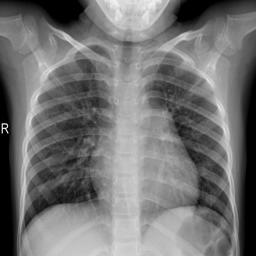

Large numbers of labeled medical images are essential for the accurate detection of anomalies, but manual annotation is labor-intensive and time-consuming. Self-supervised learning (SSL) is a training method to learn data-specific features without manual annotation. Several SSL-based models have been employed in medical image anomaly detection. These SSL methods effectively learn representations in several field-specific images, such as natural and industrial product images. However, owing to the requirement of medical expertise, typical SSL-based models are inefficient in medical image anomaly detection. We present an SSL-based model that enables anatomical structure-based unsupervised anomaly detection (UAD). The model employs the anatomy-aware pasting (AnatPaste) augmentation tool. AnatPaste employs a threshold-based lung segmentation pretext task to create anomalies in normal chest radiographs, which are used for model pretraining. These anomalies are similar to real anomalies and help the model recognize them. We evaluate our model on three opensource chest radiograph datasets. Our model exhibit area under curves (AUC) of 92.1%, 78.7%, and 81.9%, which are the highest among existing UAD models. This is the first SSL model to employ anatomical information as a pretext task. AnatPaste can be applied in various deep learning models and downstream tasks. It can be employed for other modalities by fixing appropriate segmentation. Our code is publicly available at: https://github.com/jun-sato/AnatPaste.

翻译:大量贴有标签的医学图像对于准确检测异常现象至关重要,但人工注解是劳动密集型和耗费时间的。自监学习(SSL)是一种培训方法,用于在不人工注解的情况下学习特定数据特征。一些基于SSL的模型被用于医学图像异常现象的检测。这些SSL方法有效地学习了多个特定领域图像的表解,如自然和工业产品图像。然而,由于医学专业知识的要求,基于SSL的典型模型在医学图像异常现象检测方面效率低下。我们展示了一个基于SSL的模型,可以进行基于解剖结构的、不受监督的异常现象检测(UAAD)。该模型使用解剖-觉粘贴(AnatPaste)增强工具。基于SSL的几种模型用于医学图像异常现象。这些异常现象与真正的异常相似,有助于模型识别这些异常现象。我们在三种开源的胸腔辐射数据集中可以使用模型,在基于解剖面结构结构的曲线下(AUSC),在92.1号中使用解析(Anal-SL)粘度图解为最高格式。